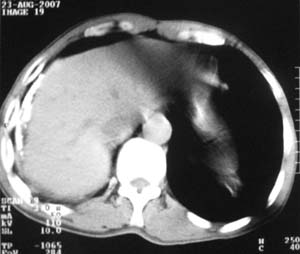

标题: CT9556:男,54岁,包裹性积液,请各位老师会诊其原因! [打印本页]

标题: CT9556:男,54岁,包裹性积液,请各位老师会诊其原因!

男,54岁,无任何不是感.体检发现右肺部阴影.现行ct进一步确诊.

包裹性积液伴胸膜钙化

右侧胸廓塌陷,肋间隙变窄,肋骨增生变粗,脏壁层胸膜肥厚、钙化。符合陈旧性结核性脓胸改变

右侧包裹性积液伴胸膜钙化.

结核性胸膜炎可能性大!脓胸!

包裹性积液伴胸膜钙化,结核性?

包裹性积液伴胸膜钙化,考虑结核性

右侧包裹性积液并胸膜钙化,性质还是结合穿刺细胞学检查的好,结核性、化脓性均会有钙化。

包裹性积液伴胸膜钙化,原因多种,国民一般为结核性居多